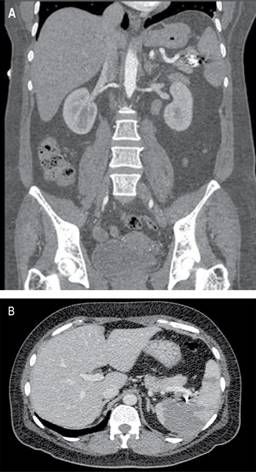

Femenino de 41 años, con antecedente de hipotiroidismo diagnosticado a los 21 años, actualmente sin tratamiento médico desde los 40 años por aparente control, diagnóstico de miomatosis uterina a los 40 años, sin tratamiento; antecedente de dos cesáreas, última a los 23 años, sin complicaciones. Accidente automovilístico con volcadura a los 40 años, sin daño orgánico aparente. Inicia padecimiento actual posterior a accidente automovilístico ocurrido un año previo con dolor en hipocondrio izquierdo, de tipo intermitente, punzante, sin irradiaciones, sin agravantes ni atenuantes; a la exploración física presenta dolor en hipocondrio izquierdo a la palpación profunda, resto sin datos patológicos. Se realizó ultrasonido con hallazgos compatibles con aneurisma de la arteria esplénica y colelitiasis, se complementa abordaje diagnóstico con angiotomografía de aorta abdominal encontrando arteria esplénica de calibre normal, con dilatación focal sacular en segmento distal compatible con aneurisma de 17.7 × 15.9 mm y cuello de 5.5 mm, con trombo mural de 2 mm, sin signos de ruptura, litiasis vesicular y miomatosis uterina. En manejo conjunto con angiología se realiza embolización selectiva con colocación de coils, sin complicaciones aparentes (Figura 1). En el seguimiento inmediato, la paciente presenta dolor abdominal y leucocitosis, se realiza nueva angiotomografía con datos sugestivos de oclusión de arteria esplénica e infarto esplénico (Figura 2). Por los hallazgos comentados se decide realizar esplenectomía y colecistectomía convencional mediante abordaje quirúrgico con incisión en línea media, supraumbilical, con los siguientes hallazgos: vesícula biliar de paredes delgadas, múltiples litos en su interior de 5-10 mm aproximadamente, arteria cística de 2 mm, conducto cístico de 3 mm, bazo de 13 × 10 cm aproximadamente, con múltiples zonas isquémicas, aneurisma de la arteria esplénica a nivel de hilio esplénico, posterior a su bifurcación (Figura 3). Cursa el postoperatorio sin complicaciones, por lo que fue egresada tres días después de la cirugía, recibió vacunación correspondiente para pacientes esplenectomizados. Reporte histopatológico con hallazgos de aneurisma de arteria esplénica con ateroesclerosis, parénquima esplénico con vasos congestivos y colecistitis crónica litiásica.

Figura 2: Angiotomografía abdominal. A) En corte coronal se identifica material de densidad metálica correspondiente a coils localizados en segmento distal de arteria esplénica previos a hilio esplénico. B) Se observa opacificación y captación del contraste a nivel esplénico de forma irregular heterogénea tanto en la fase arterial como venosa, apreciando una zona extensa que involucra a la mayor parte del parénquima esplénico desde el hilio, sólo respetando el polo superior y el inferior compatible con infarto.